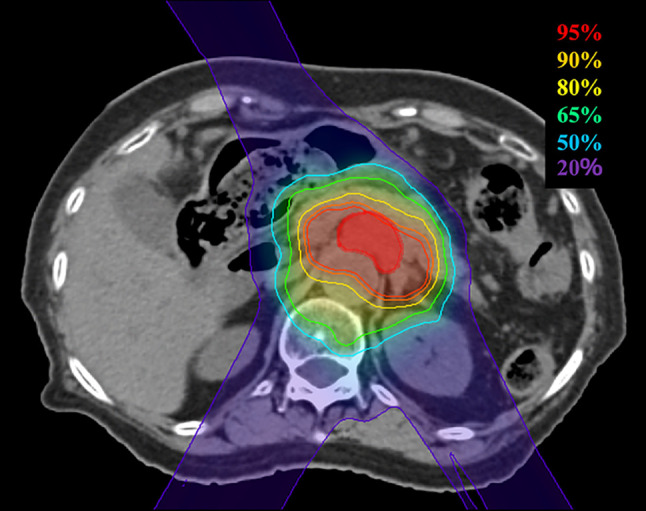

Patients and methods: This study included 10 patients with pancreatic cancer confirmed as inoperable due to locally advanced stage, comorbidity, or refusal to undergo surgery, without distant metastasis. All patients received a total PBT dose of 67.5 Gy (relative biological effectiveness) delivered in 25 fractions.

Abstract Image